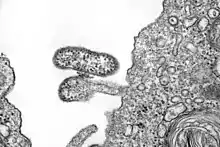

electron microscope image of Chapare virus

The Chapare virus is an enveloped virus with a bi-segmented single-stranded ambisense RNA genome. The two RNA segments are denoted Small (S) and Large (L). It belongs to the New World Clade B lineage of mammarenaviruses and is most closely related to the Sabia virus.[2][5]